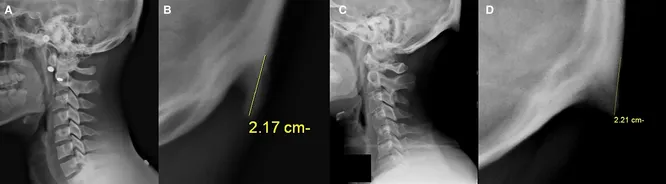

Врачи давно предупреждали подростков о надвигающейся угрозе, однако недавно мануальный терапевт Джейк Бойл (Jake Boyle) поделился в своем аккаунте в TikTok более весомыми доказательствами влияния электронных девайсов на позвоночник. Врач опубликовал рентгеновские снимки девушек и юношей с искривленной шеей, которые приходили к нему на прием в одну из клиник штата Айова.